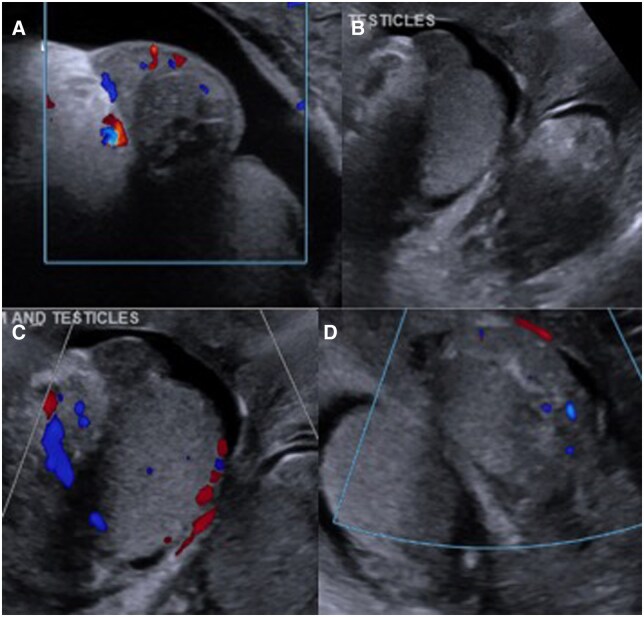

结节性多动脉炎(PAN)是一种全身性中小血管炎。它通常与乙型肝炎感染有关,典型表现为皮肤、胃肠道或神经系统受累。我们提出了一个病例56岁的男性谁提出了一个主诉的痛苦阴囊肿胀。最初的超声检查显示有附睾炎,患者开始使用适当的抗生素,但症状没有改善,因此入院。由于持续的阴囊疼痛、发烧和阴性的感染检查,F-18氟脱氧葡萄糖(FDG) PET/CT显示弥漫的高代谢活动贯穿中至小动脉血管,涉及血管炎。盆腔血管造影证实了诊断,患者开始使用类固醇并计划使用环磷酰胺。临床睾丸受累是一种罕见的PAN表现,尽管它经常在尸检中看到。以前报告的病例除了体质症状外,还表现出类似的阴囊疼痛和压痛,并使用类固醇和免疫抑制剂治疗。虽然组织病理学活检或血管造影通常是诊断PAN的金标准,但本病例也证明了F-18 FDG PET/CT在核医学诊断中的应用。结节性多动脉炎在F-18 FDG PET/CT上典型表现为中小血管的高代谢活动,最常见于下肢。由于类似的发现,本病例有助于报道核成像在诊断血管增生中的应用。

Polyarteritis nodosa (PAN) is a systemic small to medium vessel vasculitis. It is often associated with hepatitis B infection and classically presents with cutaneous, gastrointestinal, or nervous system involvement. We present a case of a 56-year-old male who presented with a chief complaint of painful scrotal swelling. Initial ultrasound demonstrated concern for epididymitis, and the patient was started on appropriate antibiotics without improvement of symptoms, resulting in admission. Due to continued scrotal pain, fevers, and negative infectious work-up, F-18 fluorodeoxyglucose (FDG) PET/CT was obtained, revealing diffuse hypermetabolic activity throughout the medium to small arterial vasculature, concerning for vasculitis. Abdominopelvic angiography confirmed the diagnosis, and the patient was started on steroids with plans to initiate cyclophosphamide. Clinical testicular involvement is a rare presentation of PAN, although it is often seen at autopsy. Previously reported cases have presented with similar scrotal pain and tenderness in addition to constitutional symptoms, as well as treatment with steroids and immunosuppressive agents. While biopsy with histopathology or angiography often serves as the gold standard for the diagnosis of PAN, this case also demonstrates the diagnostic utility of nuclear medicine with F-18 FDG PET/CT. Polyarteritis nodosa typically demonstrates hypermetabolic activity of the small- to medium-sized vasculature on F-18 FDG PET/CT, most often in the lower extremities. With similar findings, this case contributes to reports that show the utility of nuclear imaging in diagnosing vasculitides.